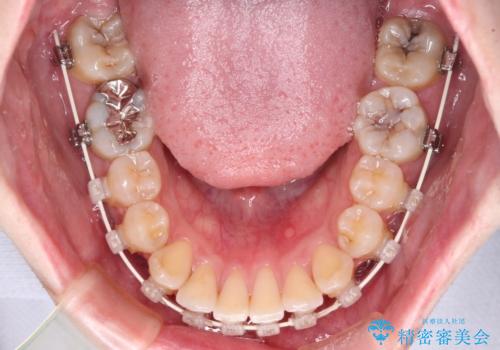

- 上下前歯のデコボコを気にして来院された患者様です。

マウスピース矯正でもワイヤー矯正でも対応可能でしたが、インビザラインによる自己管理が煩わしいとのことで、ワイヤー装置にて矯正治療を行うこととしました。

口元はやや突出感がありましたが抜歯矯正をするほどではないため、舌突出癖を改善するトレーニングをしっかりと行っていただき、現在よりも唇が閉じやすい位置に仕上げていくこととしました。

下顎前歯が思っていた以上に動きが悪く、想定よりも期間がかかってしまいました。